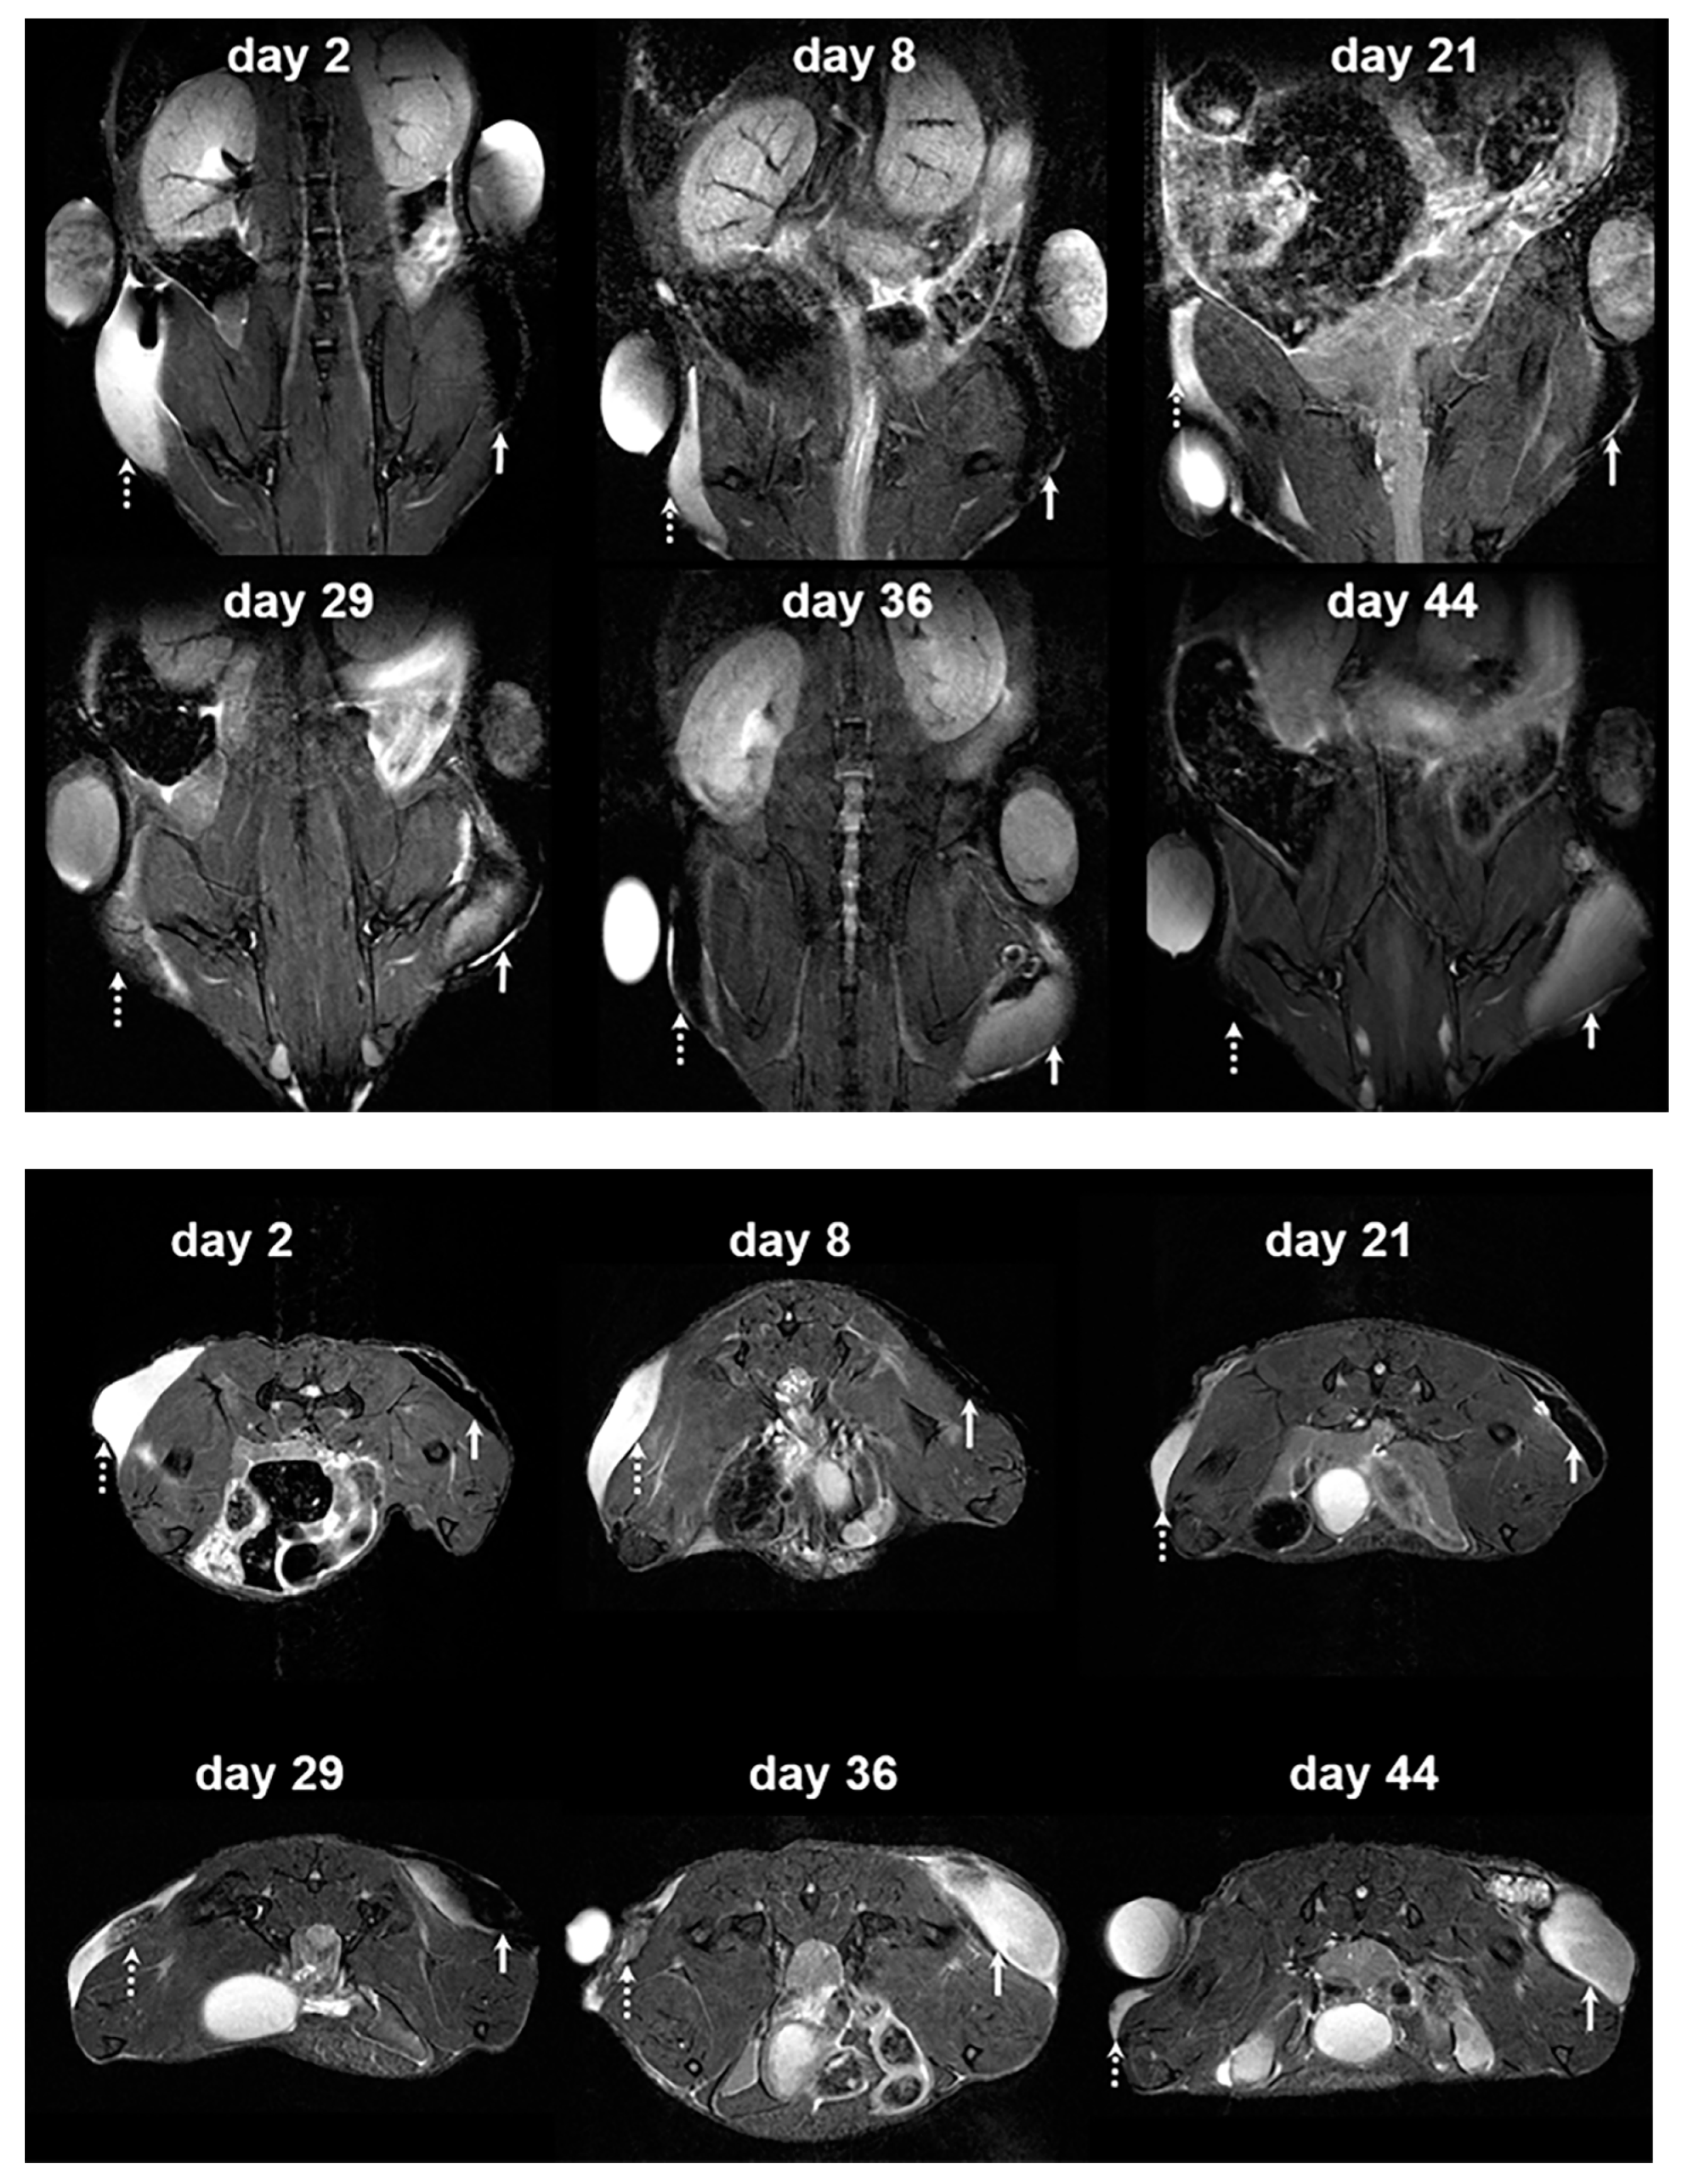

3.3. In Vivo MR Images of Hydrogel-Embedded MIN6 Cells after Subcutaneous Transplantation